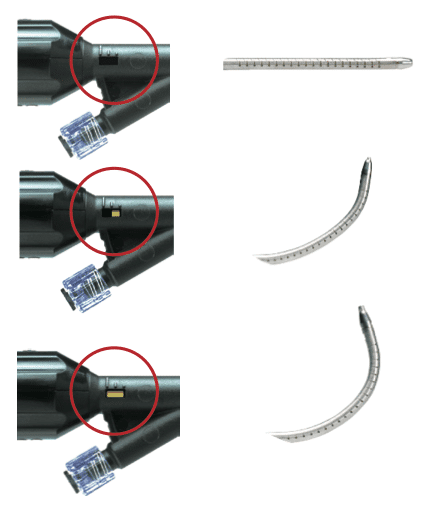

The ergonomically designed handle of the Osseoflex SN gives the physician control over the direction and articulation of the delivery needle.

ACTUATION CURVE INDICATOR

OSSEOFLEX SN/SN+ STEERABLE NEEDLE DYNAMIC RANGE OF MOTION